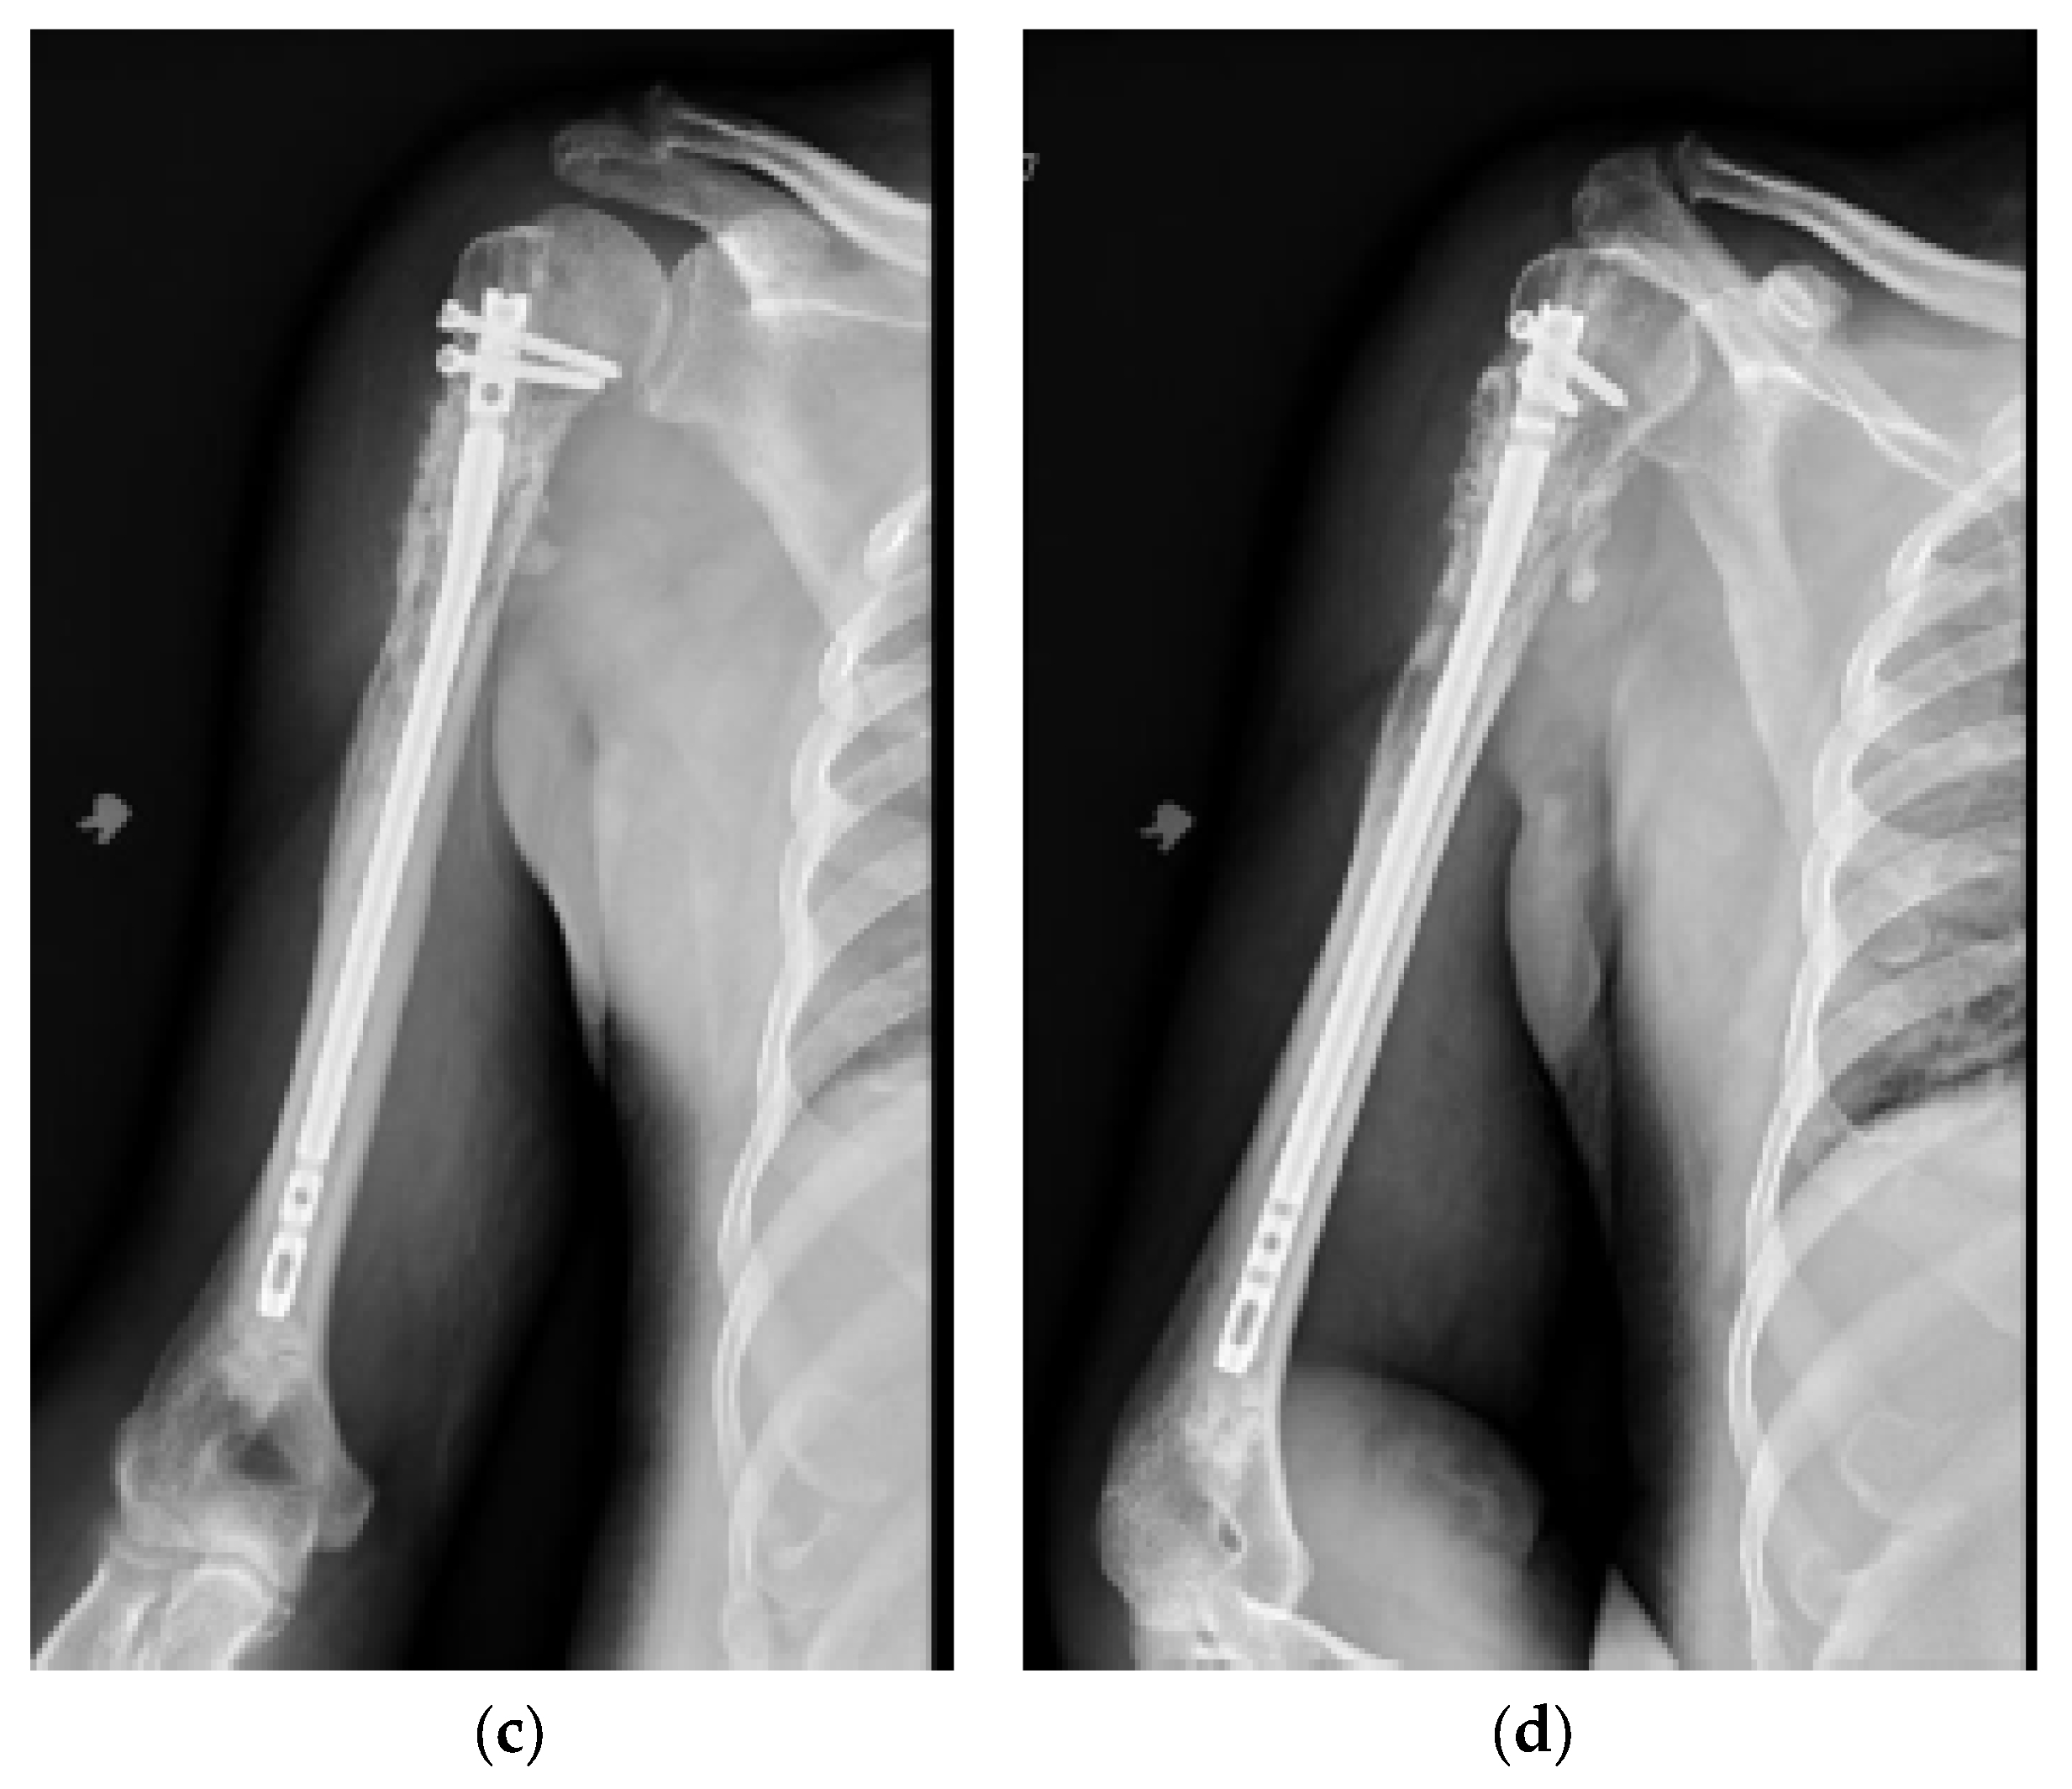

Figure 2.

(a) AP and (b) lateral right humerus radiographs of a 67-year-old male with a mixed lytic sclerotic lesion in the proximal meta-diaphyseal region, with a pathologic fracture from a newly diagnosed metastatic prostate cancer. This was treated by a bone biopsy, followed by a cemented IMN with two proximal inter-locking screws and no distal screw, as shown in the (c) AP and (d) lateral humerus radiographs. Cement was used for augmentation, due to poor proximal humerus bone quality, to support the nail and the inter-locking screws.